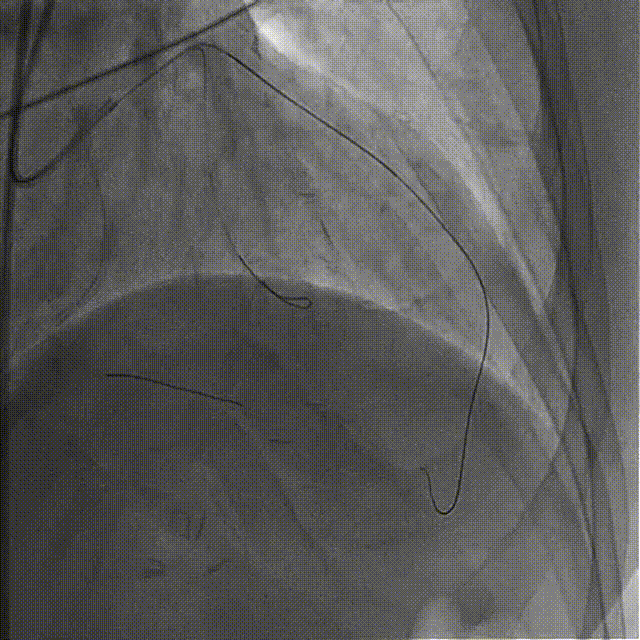

依次用Pinoeer 2.0mm x 15mm、Pinoeer 2.5mm x 15mm球囊至病变处反复扩张,送入Marvel导丝至D1远段做保护,LAD行IVUS检查。

IVUS检查示:可见导丝全程走行与血管真腔,近中段重度纤维增生斑块伴局部钙化,远段血管床废用性萎缩。

于LAD病变处由远及近依次植入XIENCE Alpine 2.5mm x 18mm和XIENCE Alpine 3.0mm x 23mm支架各一枚。